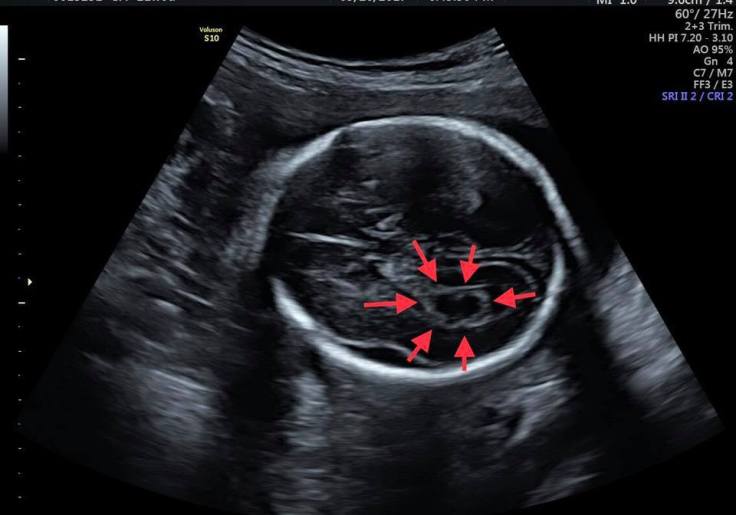

脈絡叢囊腫是指

一般在懷孕大約16到24周的時候

在超音波下發現胎兒側腦室脈絡叢內會看到的囊腫

絕大部分在26周以後會消失